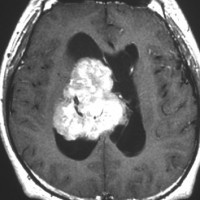

20代の男性の神経細胞腫です。側脳室の中のとても大きな腫瘍です。上段はガドリニウムという造影剤を入れた時のMRIです。下段の中央はCTですが,石灰化が見られます。脳外科の先生には,この脳室内腫瘍は一見transcallosal approach(経脳梁到達法)という手術で取れるように見えるかもしれませんが,そうではなくて,脳室の壁とくに上壁と側壁にくっついているのでなかなか取れません。この患者さんの場合は右の頭頂葉というところからtranscortical approach(経皮質到達法)で全摘出しました。後遺症もなく再発もなく術後10年が過ぎています。全部とれれば治ってしまう腫瘍です。